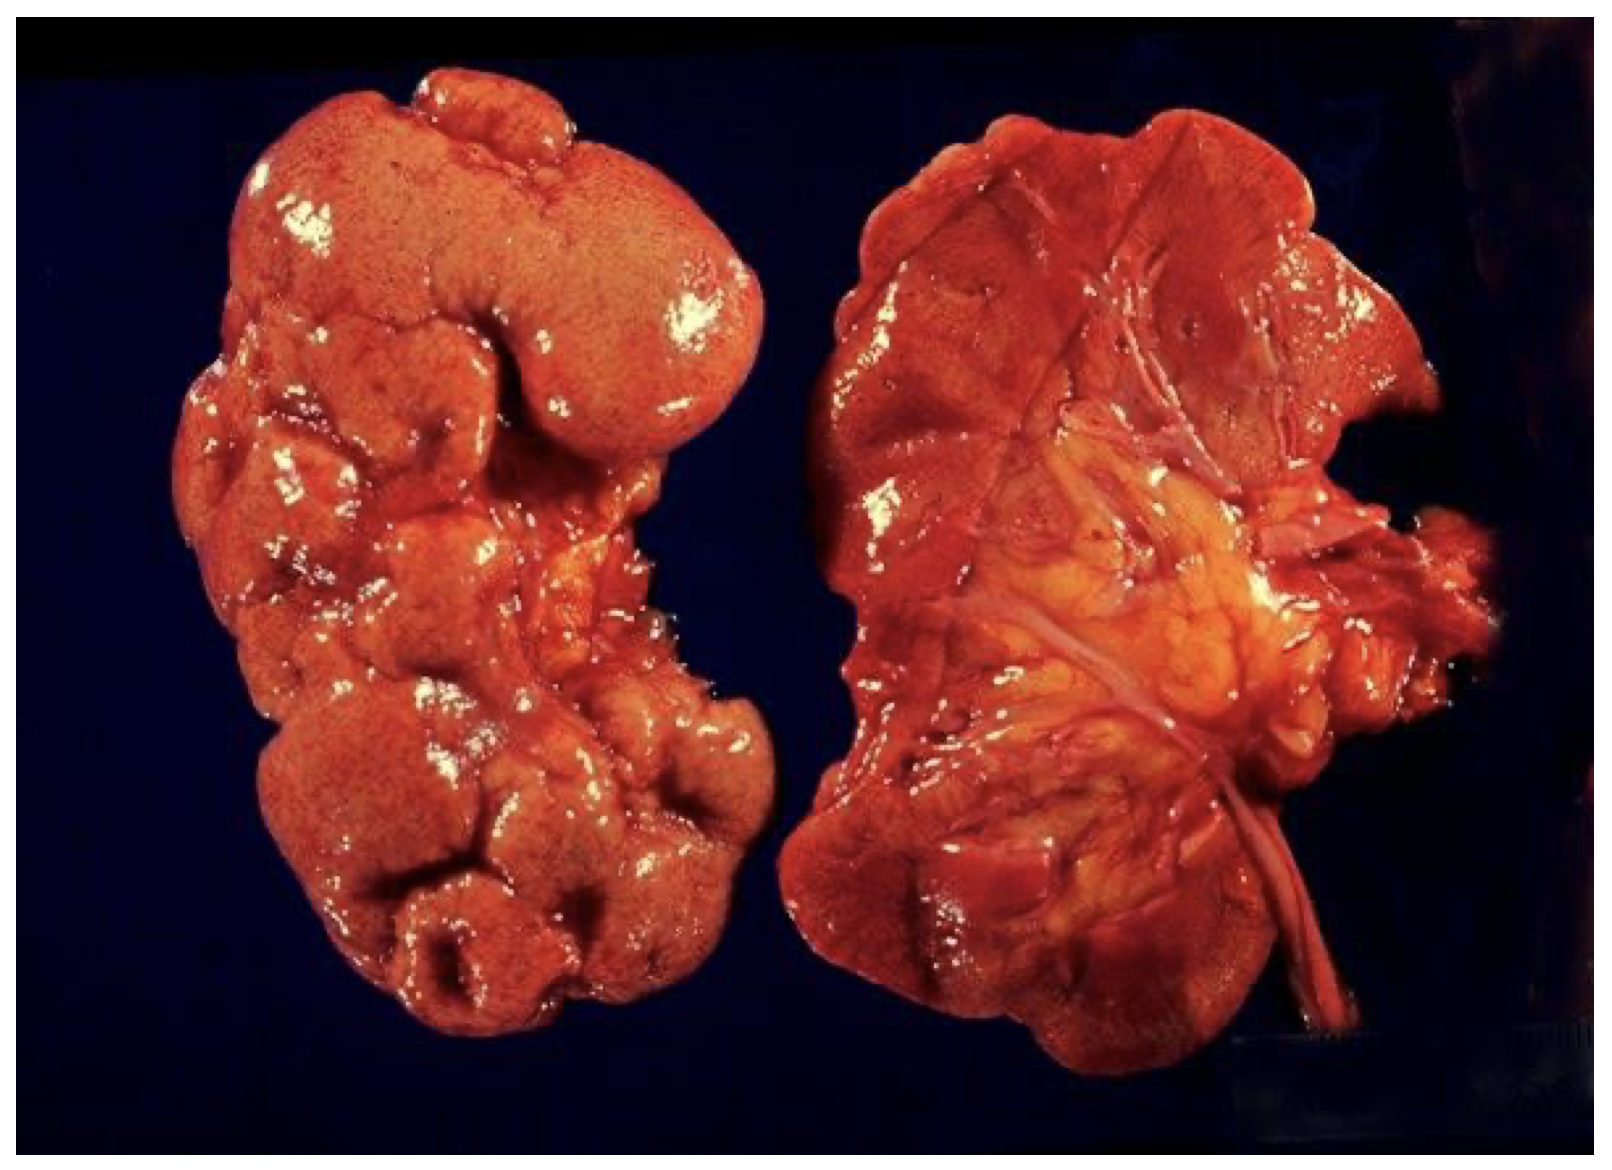

Acute pyelonephritis, gross

In acute pyelonephritis, the infection generally ascends from the bladder, although it is possible to get hematogenous spread (rare). The infection ascends into the renal tubular system. Grossly, the kidney is red and swollen (inflamed), and yellow streaks can be seen in the medulla. These correspond microscopically to tubules filled with pus.

Chronic pyelonephritis, gross

The kidney is contracted from chronic inflammation and fibrosis. In pyelonephritis, scarring is often asymmetric, versus symmetrical scarring in vascular disease. Typically, reflux may be worse in one ureter vs. the other, whereas atherosclerosis affects both kidneys equally.